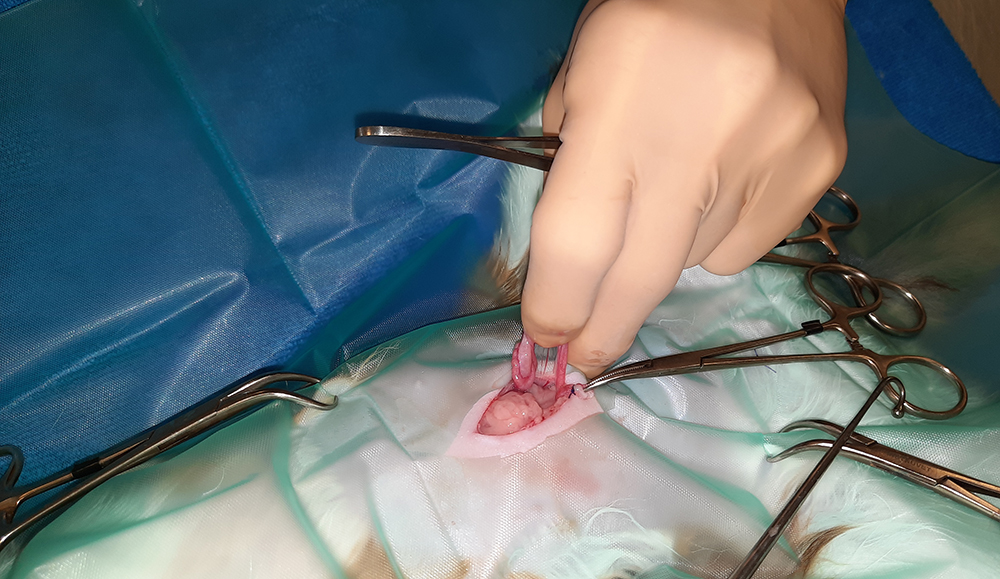

Er wordt een kleine snede gemaakt in de buik, ter hoogte van de navel. Vervolgens worden na elkaar de twee ovaria (=eierstokken) opgezocht, de aanvoerende bloedvaten afgebonden en de eierstokken verwijderd. Hierna wordt de buik in 3 lagen gesloten; de spierlaag, de onderhuid en de huid. Deze laatste wordt onderhuids gesloten met soms een enkele uitwendige knoophechting, zodat er zo min mogelijk hechtingen zichtbaar zijn. Er wordt een wondpleister geplaatst, nadat het wondgebied voorzichtig is schoongemaakt.